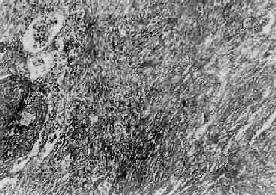

三、职业性肺疾病在职业活动、特别是生产过程中,因长期吸入有害粉尘,引起以肺广泛纤维化为主要病变的疾病,统称尘肺(pneumoconiosis)。尘肺是我国一种法定职业病。属职业性尘肺的病种较多,按粉尘的化学性质可将其分为无机尘肺和有机尘肺两大类。无机尘肺中常见的有硅肺、煤工尘肺、石棉肺等。有机尘肺是因吸入各种有机尘埃,最常见的是由霉菌的代谢产物或动物性蛋白质引起的尘肺,如农民肺、蔗尘肺、蘑菇肺、麦芽肺和饲禽者肺等。尘肺对健康危害极大,关键在于预防。改革不合理的生产过程,建立粉尘监测制度,切实落实综合防尘措施。不接触粉尘或减少吸入粉尘的机会,对于粉尘作业工人定期体检,做到早期检查、早期诊断,对已确诊为尘肺患者及早调离粉尘作业,并进行必要的治疗,完全可以控制和减少尘肺的发病率。 (一)矽肺 矽肺(silicosis)是在生产环境中长期吸入大量含游离二氧化硅(SiO2)粉尘微粒所引起的以肺纤维化为主要病变的全身性疾病。游离二氧化硅主要存在于石英中,石英成分中SiO2占97%~99%。约有70%的矿石中均含有较多的SiO2。长期从事开矿、采石作业、坑道作业以及在石英粉厂、玻璃厂、耐火材料厂、陶瓷厂和搪瓷厂生产作业的工人易患本病。矽肺是危害最严重的一种职业病,其特点是发展缓慢,即使在脱离矽尘作业后,病变仍然继续缓慢发展。患者多在接触矽尘10~15年后才发病。若因吸入高浓度、高游离二氧化硅含量的矽尘,经1~2年后发病者,称速发型矽肺。矽肺的早期即有肺功能损害,但因肺的代偿能力很强,患者往往无症状,随着病变的发展,尤其是合并肺结核和肺心病时,则逐渐出现不同程度的呼吸和心功能障碍。 【病因和发病机制】 游离二氧化硅是矽肺的致病因子。矽肺的发生、发展与矽尘中游离二氧化硅的含量,生产环境中矽尘的浓度、分散度,从事矽尘作业的工龄及机体防御功能等因素有关。矽尘粒子愈小,分散度愈度,在空气中的沉降速度愈慢,被吸入的机会就愈多,致病作用亦愈强。一般来说,大于5μm的矽尘往往被阻留在上呼吸道,并可被呼吸道的防御装置清除。小于5μm的矽尘才能被吸入肺泡,并进入肺泡间隔,引起病变。尤以1~2μm的矽尘微粒引起的病变最为严重。 吸入肺泡内的矽尘微粒被肺巨噬细胞吞噬,沿肺淋巴流经细支气管周围、小血管周围、小叶间隔和胸膜再到达肺门淋巴结。当淋巴道阻塞后,矽尘沉积于肺间质内引起矽肺病变。若局部沉积的矽尘量多,引起肺巨噬细胞局灶性聚积,可导致矽结节形成;若矽尘散在分布,则引起弥漫性肺间质纤维化。矽肺的发病机制尚未完全阐明。一般认为,矽尘被肺巨噬细胞吞噬后,在游离二氧化硅的毒性作用下,巨噬细胞大量死亡崩解或发生功能和生物学行为改变,释放出一些致纤维化因子、包括巨噬细胞生长因子(MDGF),白细胞介素Ⅰ(IL-1)和纤维连结蛋白(FN)等,促进成纤维细胞增生和胶原形成,导致纤维化。至于巨噬细胞死亡的原因,主要是由于矽尘被巨噬细胞吞噬后,存在于次级溶酶体中,矽尘表层中的SiO2逐渐与水聚合成硅酸(系一种强的成氢键化合物),其羟基基团与溶酶体膜脂蛋白结构上的受氢原子(氧、氮或硫)间形成氢键,改变了溶酶体膜的脂质分子构型,从而破坏了膜的稳定性或完整性。溶酶体膜通透性增高或破裂,其中所含的大量水解酶溢出到细胞内,导致巨噬细胞自溶崩解。巨噬细胞死亡崩解后,释出的矽尘又被其它巨噬细胞吞噬,如此反复进行,使病变不断发展、加重。这也可解释何以患者脱离矽尘作业后肺部病变仍然会继续发展的缘由。 随着免疫学的发展,大量关于矽肺免疫的研究表明,在矽肺发生、发展过程中,有免疫因素参与。根据对矽结节玻璃样变组织的生化分析,其中球蛋白含量明显高于胶原含量,而有别于一般的玻璃样变组织的成分。动物实验证明,矽肺病变的纤维化程度与浆细胞反应强度呈正相关,提示矽肺的纤维化与抗原抗体反应有关。用荧光免疫组织化学方法观察矽结节,发现在胶原纤维及其间隙中有大量γ-球蛋白沉积,主要是IgG和IgM。如将尸检取得的矽结节玻璃样变组织制成匀浆,给家兔注射后,能产生抗人γ-球蛋白抗体。有人认为,浆细胞产生的免疫球蛋白通过形成抗原抗体复合物参与矽肺的发病。对矽肺患者作体液免疫测定发现,血清中IgG和IgM浓度增高,抗肺自身抗体、抗核抗体和类风湿因子检出率也较高。但关于矽肺免疫的抗原物质目前还未提取出来,多认为有3种可能性:①矽尘作为半抗原与机体的蛋白质结合构成复合抗原;②矽尘表面吸附的γ-球蛋白转化为自身抗原;③矽尘导致巨噬细胞死亡崩解后释放自身抗原。现已有很多证据表明,巨噬细胞死亡崩解后释放抗原的可能性最大。总之,矽肺的病因是明确的,发病机制极为复杂,在发病过程中可能有多种因素参与,它们互相影响、互为因果,共同促进矽肺的发生和发展。 【病理变化】 矽肺的基本病变是肺组织内矽结节形成和弥漫性间质纤维化。矽结节是矽肺的特征性病变,结节境界清楚,直径2~5mm,呈圆形或椭圆形,灰白色,质硬,触之有砂样感。随着病变的发展,结节可融合成团块状,在团块的中央,由于缺血、缺氧而发生坏死、液化,形成矽肺性空洞(silicotic cavity)。矽结节的形成过程大致分为三个阶段:①细胞性结节,由吞噬矽尘的巨噬结胞局灶性聚积而成,巨噬细胞间有网状纤维,这是早期的矽结节;②纤维性结节,由纤维母细胞、纤维细胞和胶原纤维构成;③玻璃样结节,玻璃样变从结节中央开始,逐渐向周围发展,往往在发生玻璃样变的结节周围又有新的纤维组织包绕。镜下,典型的矽结节是由呈同心圆状或旋涡状排列的、已发生玻璃样变的胶原纤维构成(图9-22)。结节中央往往可见内膜增厚的血管。用偏光显微镜观察,可以发现沉积在矽结节和肺组织内呈双屈光性的矽尘微粒。除矽结节外,肺内还有不同程度的弥漫性间质纤维化(图9-23),范围可达全肺2/3以上。此外,胸膜也因纤维组织弥漫增生而广泛增厚,在胸壁上也可形成胸膜胼胝,甚至可厚达1~2cm。肺门淋巴结内也有矽结节形成和弥漫性纤维化及钙化,淋巴结因而肿大、变硬。

图9-23 矽肺 肺组织呈弥漫性纤维化 矽尘沿血道转运,可在肝、脾、骨髓等处形成矽结节。 矽肺的分期和病变特征 根据肺内矽结节的数量、分布范围和直径大小,可将矽肺分为三期: Ⅰ期矽肺:矽结节主要局限在淋巴系统。肺组织中矽结节数量较少,直径一般在1~3mm,主要分布在两肺中、下叶近肺门处。X线检查,肺野内可见一定数量的类圆形或不规则形小阴影,其分布范围不少于两个肺区。此时,肺的重量、体积和硬度无明显改变。胸膜上可有矽结节形成,但胸膜增厚不明显。 Ⅱ期矽肺:矽结节数量增多、体积增大,可散于全肺,但仍以肺门周围中、下肺叶较密集,总的病变范围不超过全肺的1/3。X线表现为肺野内有较多量直径不超过1cm的小阴影,分布范围不少于四个肺区。此时,肺的重量、体积和硬度均有增加,胸膜也增厚。 Ⅲ期矽肺(重症矽肺):矽结节密集融合成块。X线表现有大阴影出现,其长径不小于2cm,宽径不小于1cm,此时,肺的重量和硬度明显增加。解剖取出新鲜肺标本可竖立不倒(图9-24),切开时阻力甚大,并有砂粒感。浮沉试验,全肺入水下沉。团块状结节的中央可有矽肺空洞形成。结节之间的肺组织常有明显的灶周肺气肿,有时肺表面还可见到肺大泡。